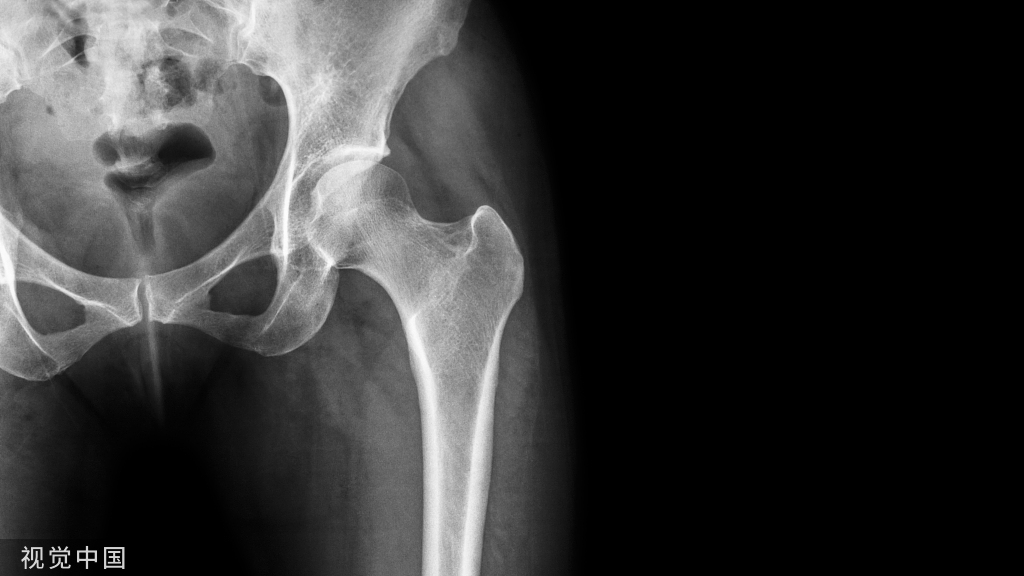

AAOS指南(2022):老年髋部骨折的16条临床诊断建议

2022年10月,美国骨科医师协会(The American Academy of Orthopaedic Surgeons,AAOS)推出了老年髋部骨折的的临床诊疗建议,其中包含11条强烈推荐建议与5条中等推荐建议。供临床参考。

老年(>55岁)髋部骨折是巨大的公共卫生问题,美国每年有32.5万例髋部骨折患者,其中2/3为女性。老年髋部骨折患者1年内死亡率超过同龄人预期死亡率的3倍,其住院期间的总医疗费用及后续护理费用,是社会的沉重负担。通过推出髋部骨折的诊疗指南,规范老龄髋部骨折的治疗,以降低骨折相关并发症,显得至关重要。